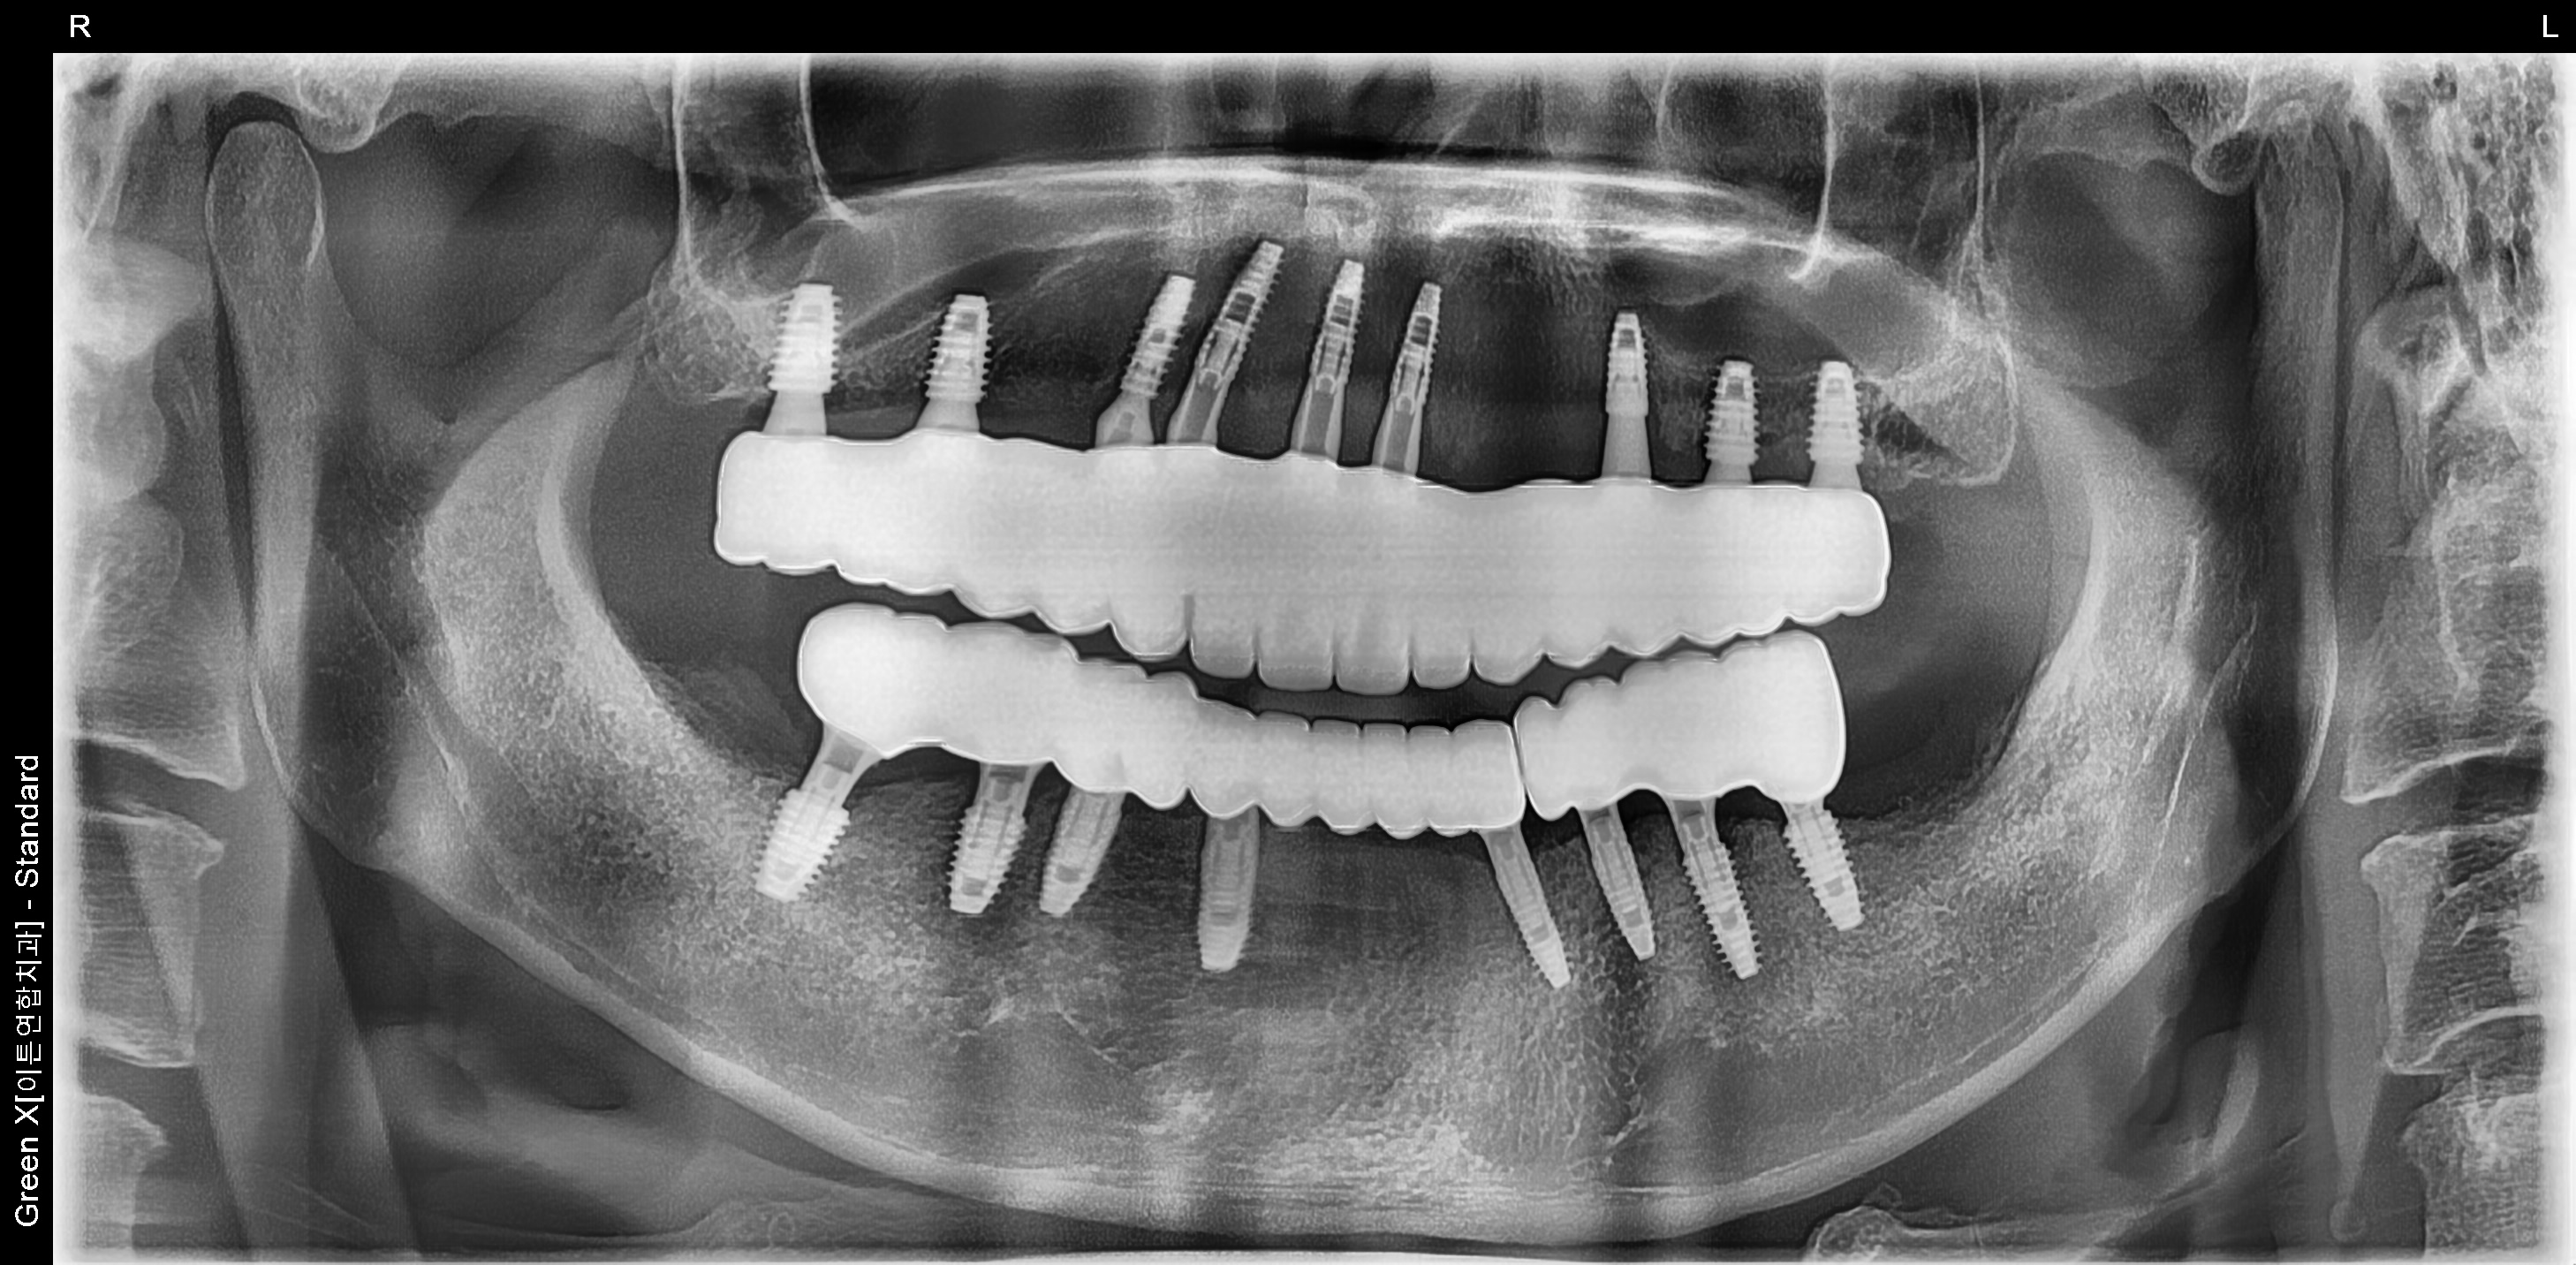

환자명 : 사OO

2025.05.26 업데이트

수술 후 촬영일자 : 2025.02.20

환자명 : 이OO

수술 후 촬영일자 : 2025.03.07

*해당 이미지는 의료법 제57조 동법 시행령을 준수하여 본원에서 직접 촬영했습니다.

치료 전후 사진은 환자분의 동의하에 동일 조건, 인물을 촬영 한 사진을 인위적인

수정 없이 사용해 일반적인 치과 치료 정보를 제공할 목적으로 게시되었습니다.

모든 시술은 개인에 따라 차이가 있을 수 있으며, 부작용이 발생할 수 있으니 의료진과

충분한 상담 후 진행하셔야 합니다.